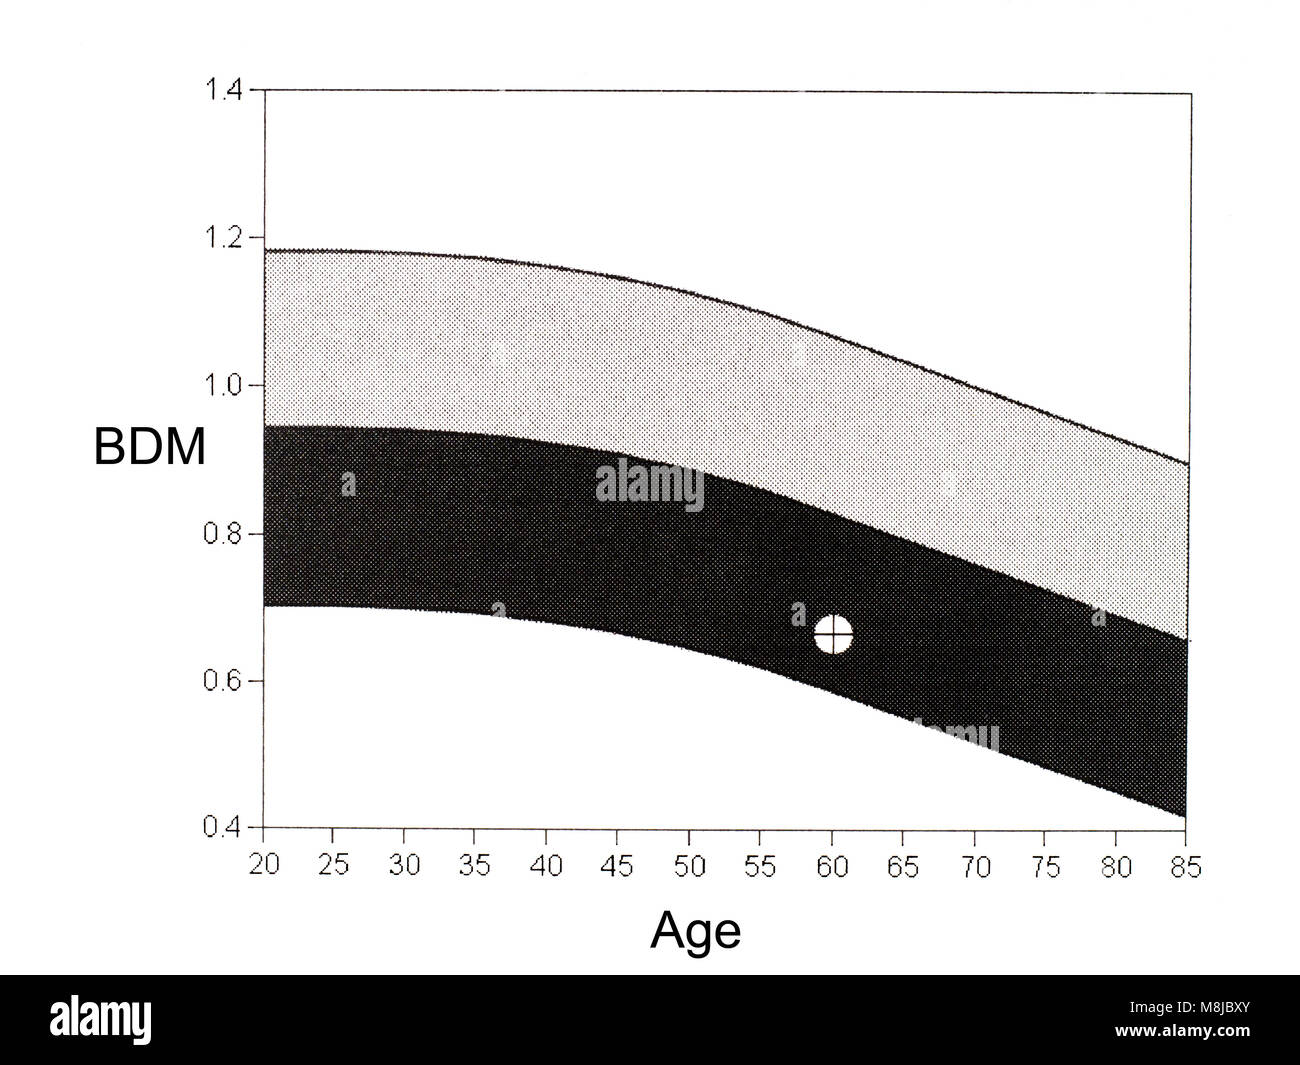

Bone density from DEXA scan. Medical technology, diagnosis osteoporosis. Stock Photohttps://www.alamy.com/image-license-details/?v=1https://www.alamy.com/stock-photo-bone-density-from-dexa-scan-medical-technology-diagnosis-osteoporosis-177425449.html

Bone density from DEXA scan. Medical technology, diagnosis osteoporosis. Stock Photohttps://www.alamy.com/image-license-details/?v=1https://www.alamy.com/stock-photo-bone-density-from-dexa-scan-medical-technology-diagnosis-osteoporosis-177425449.htmlRFM8JBY5–Bone density from DEXA scan. Medical technology, diagnosis osteoporosis.

Bone density from DEXA scan. Medical technology, diagnosis osteopenia. Frequently precursor to osteoporosis. Stock Photohttps://www.alamy.com/image-license-details/?v=1https://www.alamy.com/stock-photo-bone-density-from-dexa-scan-medical-technology-diagnosis-osteopenia-177425443.html

Bone density from DEXA scan. Medical technology, diagnosis osteopenia. Frequently precursor to osteoporosis. Stock Photohttps://www.alamy.com/image-license-details/?v=1https://www.alamy.com/stock-photo-bone-density-from-dexa-scan-medical-technology-diagnosis-osteopenia-177425443.htmlRFM8JBXY–Bone density from DEXA scan. Medical technology, diagnosis osteopenia. Frequently precursor to osteoporosis.

Osteopenia present. DEXA bone density scan, densitometry. Stock Photohttps://www.alamy.com/image-license-details/?v=1https://www.alamy.com/stock-photo-osteopenia-present-dexa-bone-density-scan-densitometry-177425434.html

Osteopenia present. DEXA bone density scan, densitometry. Stock Photohttps://www.alamy.com/image-license-details/?v=1https://www.alamy.com/stock-photo-osteopenia-present-dexa-bone-density-scan-densitometry-177425434.htmlRFM8JBXJ–Osteopenia present. DEXA bone density scan, densitometry.